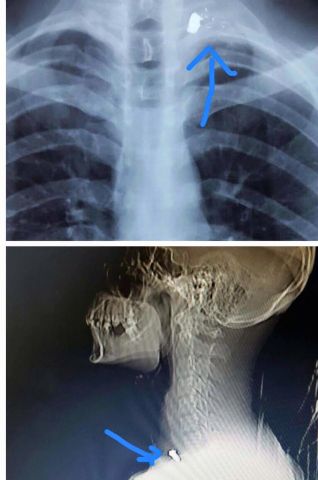

نابلس- أجريت في المستشفى الإنجيلي العربي عملية جراحية معقدة ومركبة في العنق للشاب أحمد نصاصرة (23 عاما) والذي أصيب برصاص الاحتلال في بلدة بيت فوريك شرق نابلس، حيث تكللت العملية بالنجاح.

ووصفت العملية بالمعقدة والمركبة في العنق نظرا لكون الرصاصة استقرت في أسفل العنق في منطقة قريبة من الشرايين الخارجة من القلب وسلسلة الاعصاب المغذية والأوردة الرئيسية في العنق والقصبة الهوائية والبلعوم وهي منطقة حساسة جدا .

نجحت العملية التي تم خلالها استئصال الرصاصة يوم الخميس 2015-12-31 وأخرج المريض إلى منزله يوم السبت 2016-1-2 بدون خلل عصبي أو عجز وظيفي .